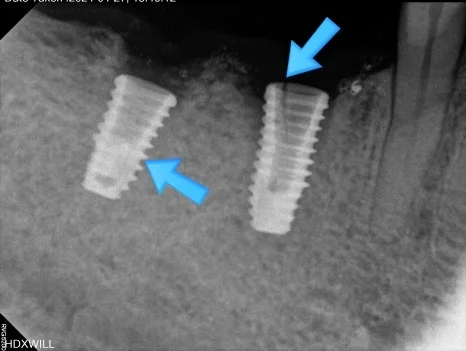

화살표로 표시된 부분을 보면 왼쪽은 내부에 무언가 남아 있는 것처럼 보이고, 오른쪽은 금이 간 듯한 모습이 확인됩니다.

정확한 상태를 확인하기 위해 우측 사진에서 가운데 지대주를 제거한 뒤 다시 촬영을 진행했습니다.

그 결과 화살표로 표시된 부분을 보면 왼쪽 임플란트는 나사 부위가 부러져 있었고, 오른쪽 임플란트는 본체에 금이 생긴 상태였습니다.